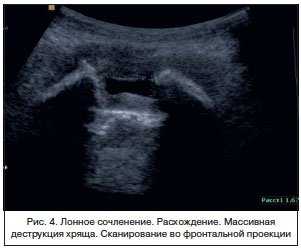

Наибольший интерес представляет исследование 3 группы — пациенток с клиническими проявлениями дисфункции ЛС во время беременности. У 60 беременных с разной степенью выраженности болевого синдрома и ограничения движения при традиционном обследовании достоверные отличия ширины ЛС от нормы, признаки расхождения лона, выявлены в 2 (3,3%) наблюдениях (рис. 4). Результаты измерений представлены в таблице 3.

УЗИ ЛС проводили во фронтальной (рис. 3) Рисунок 3. Лонное сочленение. УЗ-сканирование во фронтальной проекции. и сагиттальной (рис. 4) Рисунок 4. Лонное сочленение без признаков дисфункции. УЗ-сканирование в сагиттальной проекции. проекциях при помощи трансабдоминального конвексного мультичастотного датчика с частотой 2-6 МГц или линейного датчика 5-12 МГц. Использование линейного датчика ограничено у тучных пациенток. Проводились измерения высоты, толщины симфиза и ширина его в верхней и нижней трети. Кроме того, мы исследовали площадь сечения межлобкового хрящевого диска (discus interpubicus), отношение этой величины к площади сечения всего сочленения, размер хрящевого пояса лобкового симфиза. Полученные результаты сравнивали с ранее полученными рентгенологическими и эхографическими данными. В качестве дополнительного метода исследования изучалась эхоплотность хрящевой межлобковой пластинки у женщин. Построение гистограмм плотности тканей ЛС у всех пациенток обследованных групп проводилось в одинаковых режимах сканирования. Гистограмма представляет собой тип диаграммы, отражающей распределение эхосигналов и позволяет сравнивать относительную плотность ткани по уровню градации «серой шкалы» в условных единицах. Учитывая максимальную зависимость получаемых значений эхоплотности от индивидуальных настроек аппарата, считали целесообразным использование не абсолютных показателей данного параметра, а относительных условных единиц. В основу математической обработки материала были положены непараметрические методы математической статистики с вычислением медианы интерквартильного размаха (значений 25-го и 75-го перцентилей) для каждого показателя. Сравнение групп наблюдения друг с другом производили с помощью ряда непараметрических критериев (Вилкоксона-Манна-Уитни, Смирнова, Фишера, χ 2 ).